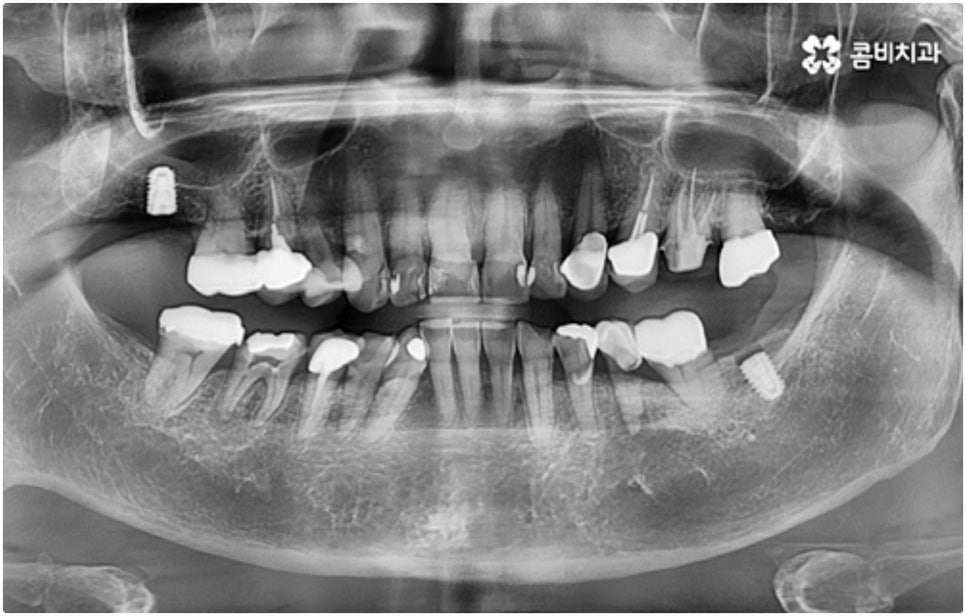

치아 상실에 대처하는 방법에는 여러 가지가 있으나 요즘 가장 각광받고 있는 치료법은 임플란트 시술로, 이는 높은 저작력 회복률과 우수한 심미성으로 원래 가지고 있던 자연 치아와 비슷하게 수복이 가능하다는 장점을 가지고 있어요.

임플란트 시술이 환자분들의 잇몸뼈에 직접 고정을 시키는 방법인 만큼 개개인의 치주 상태, 구강 내부 구조 등을 면밀하게 살펴보고 치료 계획을 세워야 하며 그 밖에도 치아가 빠진 지 얼마의 시간이 흘렀는지, 장기적으로 복용 중인 약이 있는지 등 영향을 줄 수 있는 모든 관련 상황을 종합적으로 고려하여 환자분들에게 딱 맞는 어금니임플란트 시술을 무리하지 않게 진행하는 것이 중요한 체크 포인트라고 할 수 있는데요. 그렇기 때문에 먼저 3D CT를 이용한 정밀한 검사를 통해 어떤 종류의 임플란트를 어떻게 진행할지 신중하게 검토해야 하며 또한 풍부한 노하우와 뛰어난 기술력을 갖추고 있는 의료진과 함께 충분한 사전 상담을 하실 필요가 있습니다.

하루 빨리 불편함을 덜고자 하는 마음에 전체 어금니임플란트 시술 기간이 얼마나 되는지 문의주시는 분들이 많이 있는데요. 보통 임플란트 시술은 3~6개월 정도 걸리지만 환자분들의 상황에 따라서 어금니임플란트 시술을 받기 전에 다른 치료를 먼저 해 줄 필요가 있다면 8개월 넘게 걸릴 수도 있어요.

식립 성공률 및 지속적인 안정성을 높이기 위해서는 초기 고정이 잘 이루어져야 하는데 만약에 식립 바탕이 되는 잇몸뼈의 상황이 좋지 않다면 이와 관련된 치료를 먼저 해 줘야 하는 거예요. 예를 들어 치주 질환이 심하다면 이를 깨끗하게 치료해 주는 것이 우선시 되어야 하고, 잇몸뼈의 높이나 밀도 등이 부족한 경우에는 뼈이식 과정을 통해 이를 먼저 보충해 줄 필요가 있어요. 또한 윗어금니가 빠진지 오랜 시간이 지나 이미 골흡수가 일어나고 상악동이 많이 내려와 있다면 상악동 거상술 및 뼈이식을 한 후 임플란트 식립을 진행해야 할 거예요.

어금니는 저작력이 많이 걸리는 치아이기 때문에 보철물 제작에 있어서도 강한 자극에 잘 견딜 수 있는 튼튼한 재질을 고르는 것이 중요한데 요즘은 이러한 내구성과 함께 심미적인 부분도 함께 고려하는 추세라서 어금니임플란트 시술시 지르코니아 크라운을 선택하시는 분들이 많이 있습니다.

또한 자체 기공소를 갖추고 있는 치과라면 의료진과의 긴밀한 협조를 통해 보다 빠른 시간 내에 좀 더 잘 적응할 수 있는 맞춤 보철물 제작이 가능할 것이기 때문에 환자분들의 불편을 덜어주는 데 도움을 주는 이런 사항들 역시 꼼꼼하게 체크해 보시길 권유드리고 있어요.